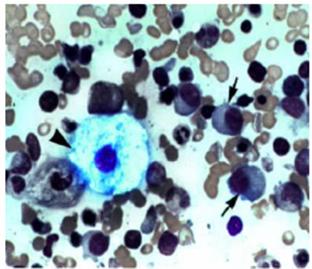

Nell'immagine è presente la cellula di Gaucher con i vacuoli che contengono materiale di accumulo.. Il tipo 1 è più frequente, questi pazienti non presentano ritardo mentale e possono vivere fino ad 80 anni.